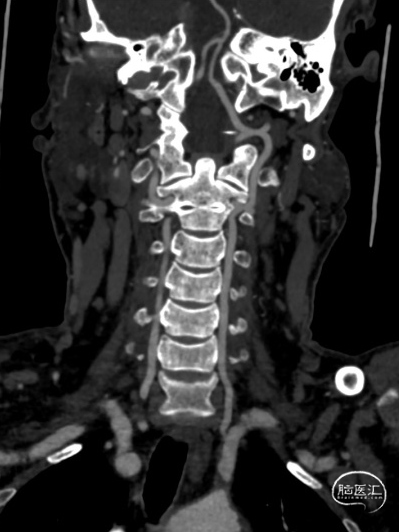

02、术前影像

头颅MR未见明显病灶。

1. 锁骨下动脉闭塞(左侧,伴盗血)

右侧椎动脉造影提示左侧锁骨下动脉盗血,左侧锁骨下动脉闭塞,近端残端较圆钝。